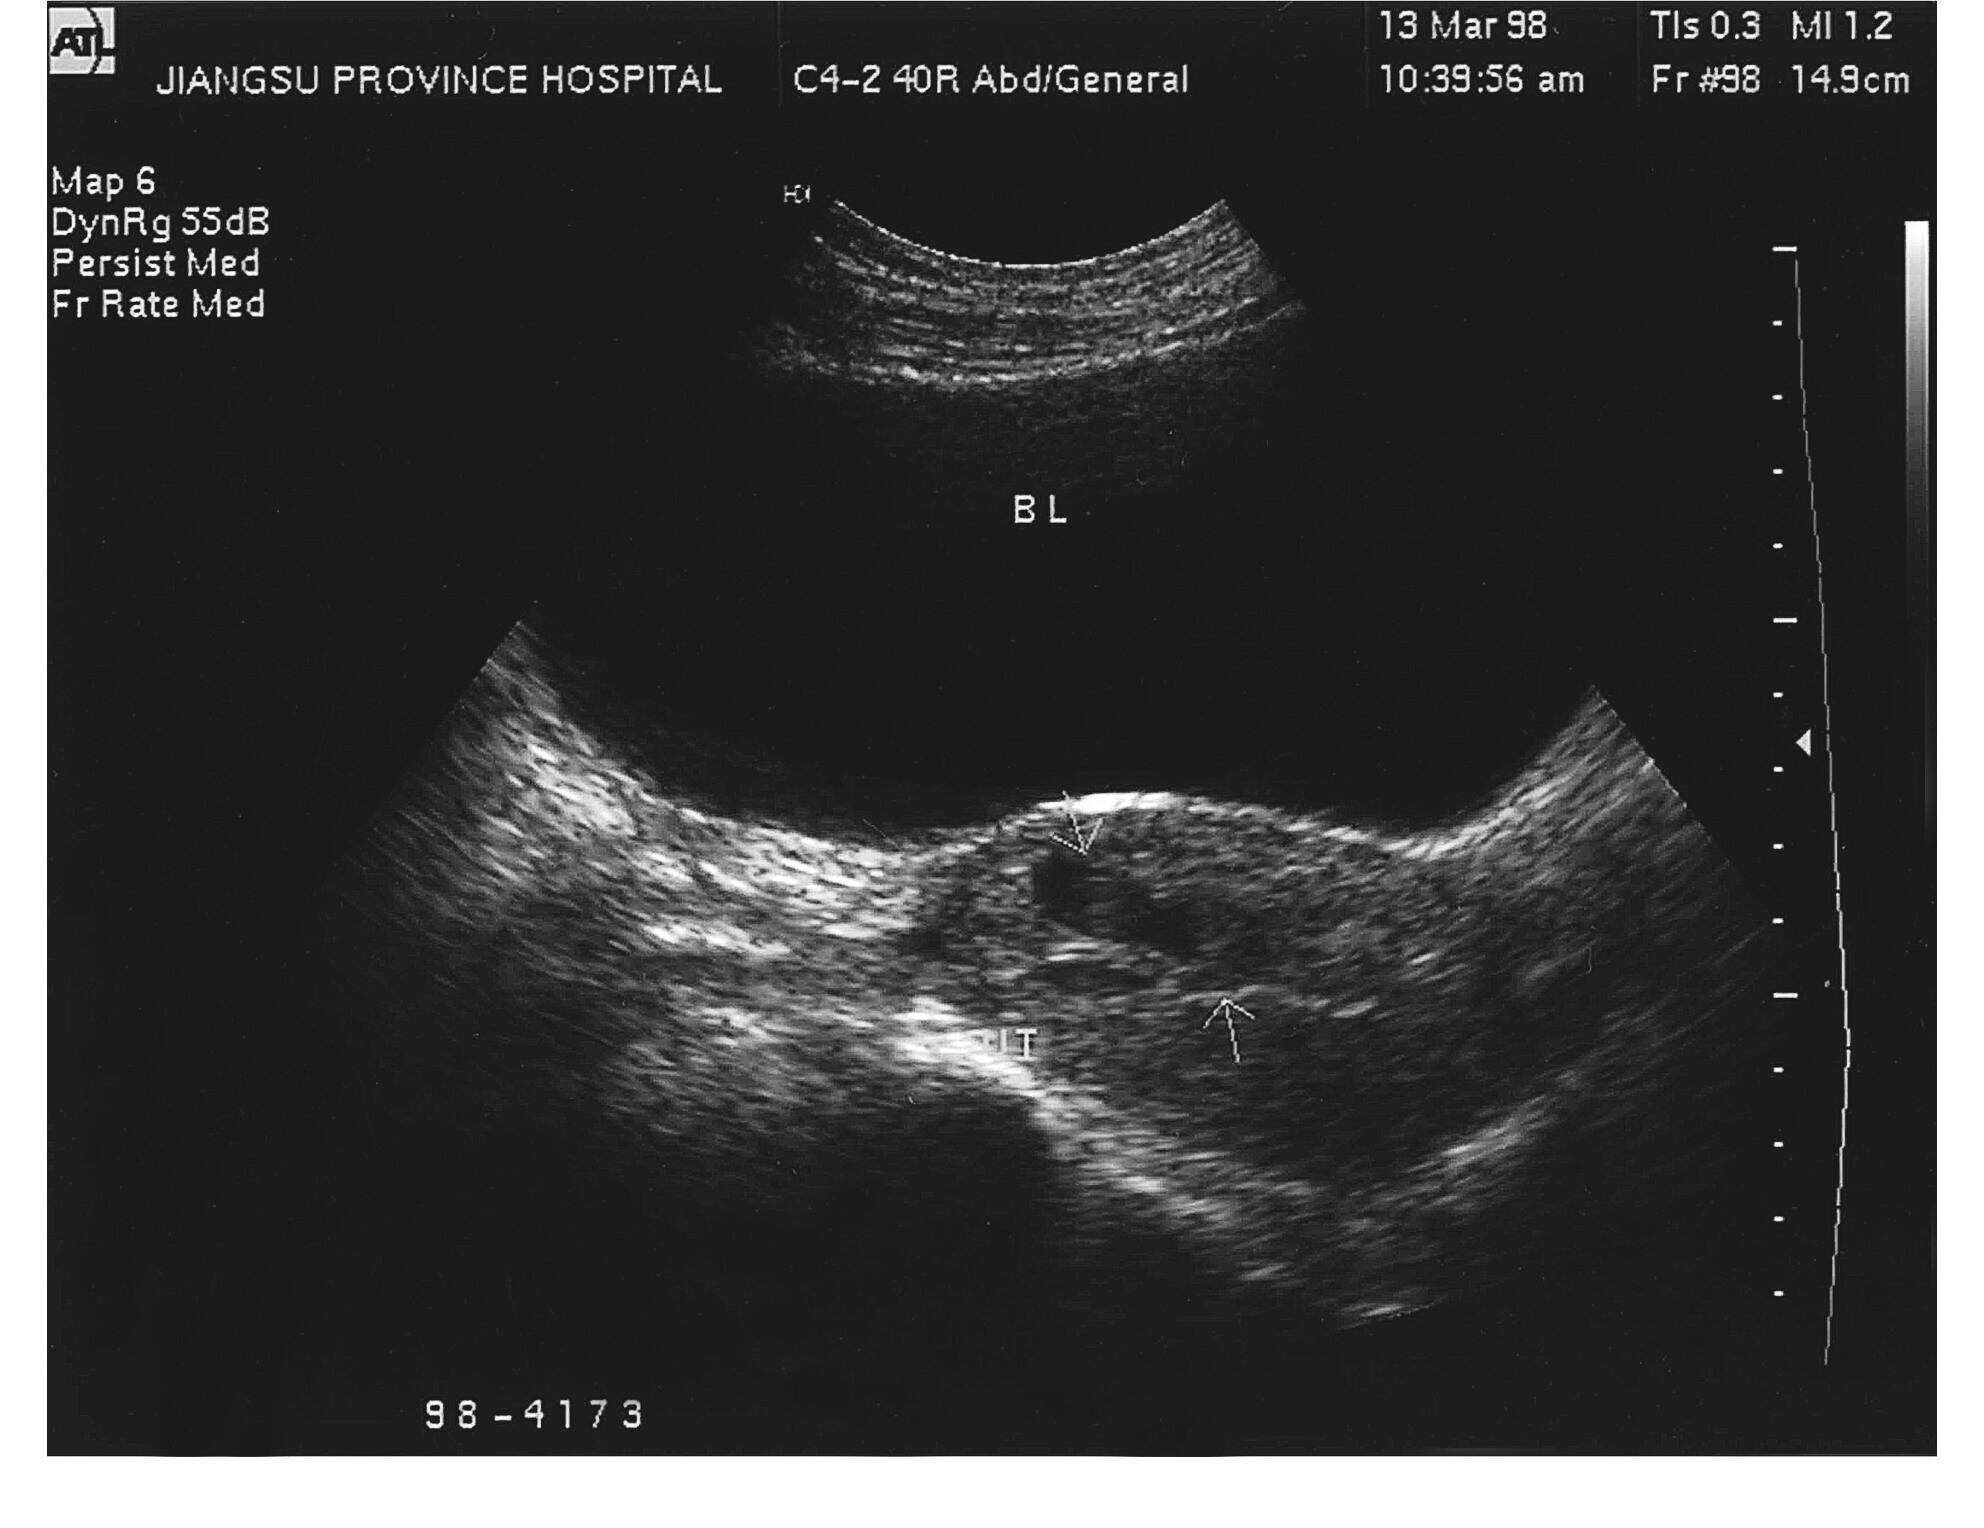

子宫 侵袭性葡萄胎

侵蚀性葡萄胎

侵蚀性葡萄胎?